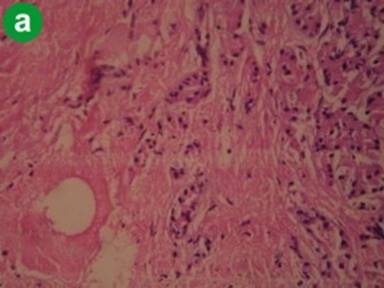

Tropical Calcific Pancreatitis

H&E staining showed atrophic acini and increased stromal component consistently in all the specimens and also prominent dilated ducts and mononuclear inflammatory cell infiltrates (Figure 1a). Immunohistochemistry with α-SMA showed dense and diffuse staining pattern in areas of fibrosis. Periacinar and periductal staining was noted. Positive staining was also present in the wall of vessels and ducts (Figure 1b). Staining with CD34 showed no or sparse positivity in the areas of fibrosis, but stained areas were observed in smooth muscle components of blood vessels and ducts (Figure 1c). These observations suggest that activated stellate cells are extensively present in the areas of fibrosis. The diffuse staining pattern represents the elongated cytoplasmic processes of PSCs extending extensively in the fibrotic areas and also into the periacinar spaces. However, the extent of staining was variable from patient to patient and only sparse staining was present in some cases.

Figure 1. Representative staining pattern observed in cases tropical calcific pancreatitis (a. H&E, b. α-SMA, c. CD34). |